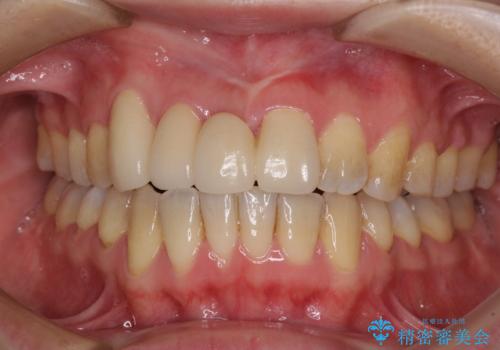

総合歯科診療(着色歯と歯並びの改善)

初診から終了まで1年3ヶ月で、特に矯正歯科治療は被せ物に換える前提であったため8ヶ月間で終了することができました。

矯正歯科治療により、かみ合わせや歯並びを改善することができ、最も気にされていた歯の変色を自然な歯の色に仕上げることができ、大変満足していただけました。